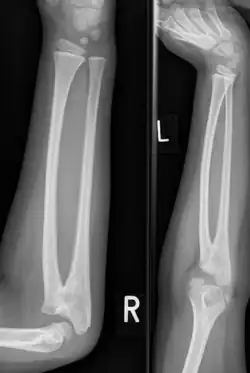

| Congenital radioulnar synostosis in a 7-year-old boy | |

Radioulnar synostosis is a rare condition where there is an abnormal connection (synostosis) between the radius and ulna bones of the forearm.[1] This can be present at birth (congenital), when it is a result of a failure of the bones to form separately, or following an injury (post-traumatic).[2]

It typically causes restricted movement of the forearm, in particular rotation (pronation and supination), though is usually not painful unless it causes subluxation of the radial head.[1] It can be associated with dislocation of the radial head which leads to limited elbow extension.[2]

Diagnosis at birthday is best done using ultrasound technology. In younger children and adults, diagnosis is done with x-ray machine at the radioulnar bones.